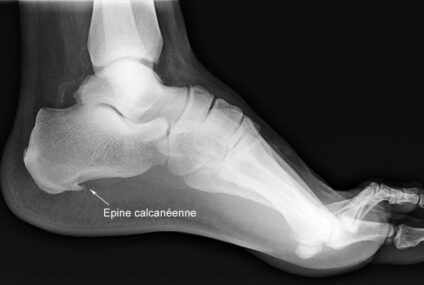

L’épine calcanéenne, ou épine de Lenoir, est une petite excroissance osseuse qui se forme sous l’os du talon. Elle est souvent liée à une inflammation de l’aponévrose plantaire, le tissu qui soutient la voûte du pied.

Le diagnostic repose principalement sur l’examen clinique, complété si besoin par une radiographie. Le surpoids, les chaussures inadaptées, les sports à impact et la station debout prolongée figurent parmi les principaux facteurs de risque.